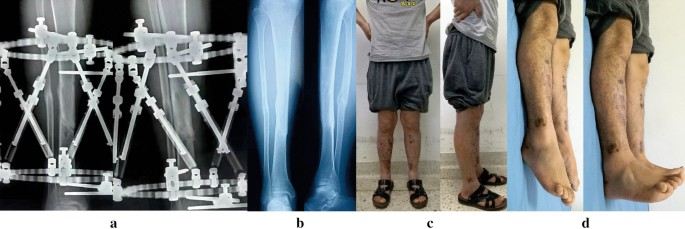

All patients (100%) achieved bone union with a mean time of 26 weeks (range 15 to 52 weeks). Primary fracture union was observed in 28 patients (82%) with a mean time of 24 weeks (range 15 to 32 weeks). Three patients (9%) suffered bone loss due to debridement and were successfully managed by acute shortening and relengthening, the mean time to healing was 31 weeks (range 28 to 35 weeks). In these 3 cases, bone lengthening and anatomic alignment were achieved by the HEF strut adjustments. The other 3 patients (9%) required further intervention procedures and united at a mean of 43 weeks (range 37 to 52 weeks). All patients were followed for an average of 15 weeks (range 12 to 26 weeks) after removing the TSF. (Figs. 1, 2, 3, 4).

Images of the same patient shown in Fig. 3. a Radiographs after 6 months from TSF application, revealing hone healed. b Radiographs 6 months later after removal of TSF. c, d Clinical follow-up images, obtained at 13 months after TSF removal